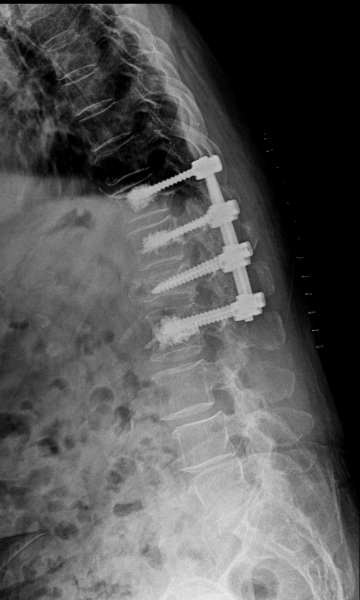

수술

치료

척추 고정술 치료 방법

2020.06.09

2020.08.11

ㆍ환자 동의를 받은 자료이며, 이미지 사진은 실물과 다를 수 있습니다.

ㆍ모든 자료는 새움병원 자료입니다.